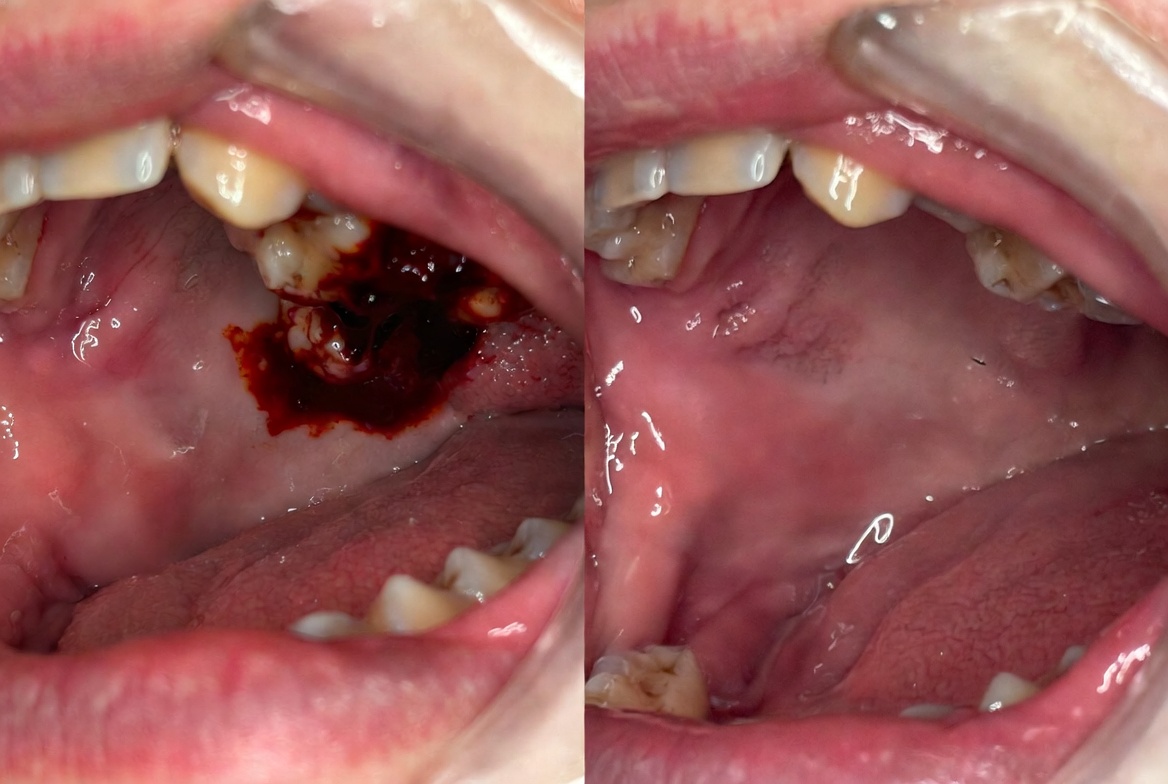

Your dentist takes a CBCT scan to map the exact position, angle, and proximity to the inferior alveolar nerve of each wisdom tooth. Local anaesthesia or IV sedation is administered. Simple extractions are performed with an elevator and forceps. Surgical extractions involve a gingival flap and bone removal for access. The socket is irrigated and sutured. Full aftercare instructions are provided with prescription pain medication and antibiotics if required.